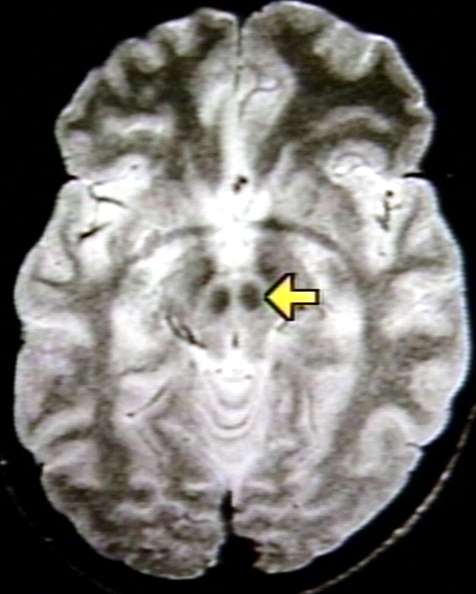

RADIOLOGY: NERVOUS: MIDBRAIN: RED NUCLEUS; 14/18 (MRI)

RADIOLOGY: NERVOUS: MIDBRAIN: RED NUCLEUS; 14/18 (MRI)